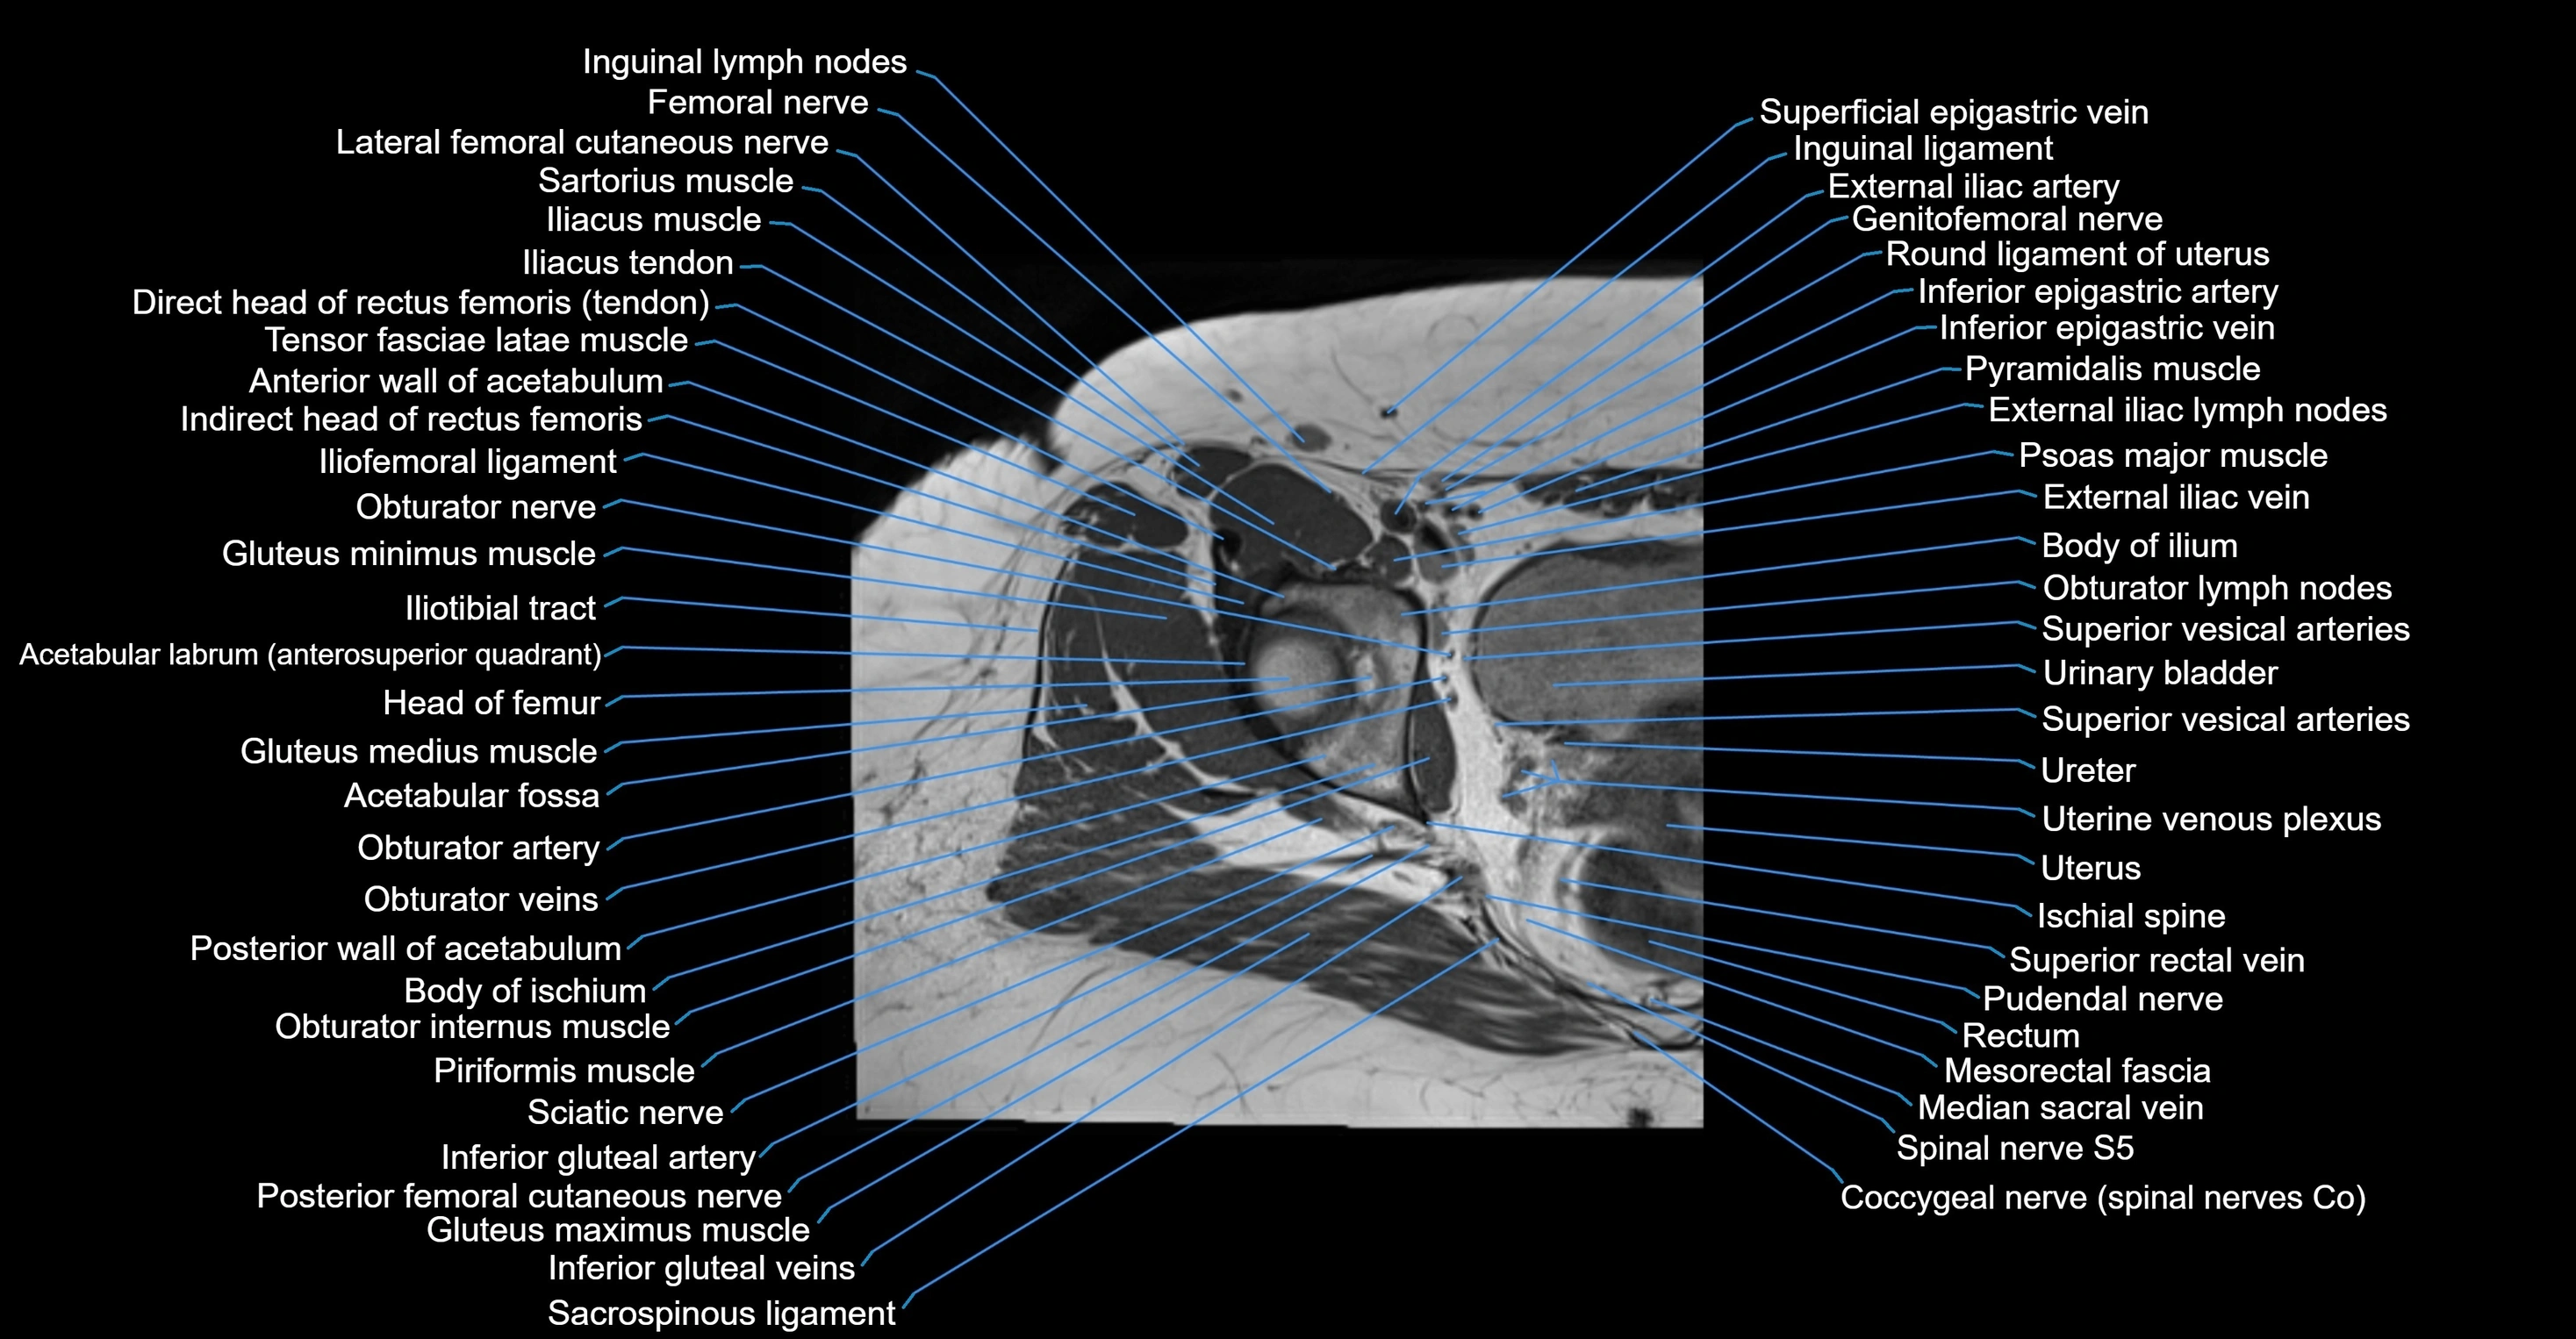

- Femoral nerve

- External iliac artery

- External iliac vein

- Urinary bladder

- Uterus

- Rectum

- Pudendal nerve

- Obturator lymph nodes

- Obturator nerve

- Inguinal lymph nodes

- Inguinal ligament

- Pyramidal muscle (pyramidalis muscle)

- Psoas major muscle

- Sacrospinous ligament

- Superior rectal vein

- Spinal nerve S5

- Obturator internus muscle

- Levator ani muscle

- Superior gemellus muscle

- Gluteus maximus muscle

- Gluteus medius muscle

- Gluteus minimus muscle

- Iliotibial tract